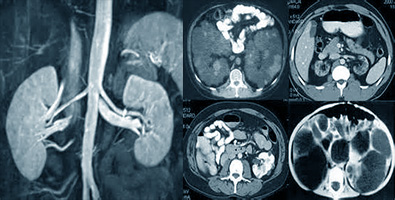

Брюшная полость и забрюшинное пространство включает в себя ряд основных органов жизнедеятельности. К брюшной полости относятся: печень с желчевыводящими путями, поджелудочная железа, желудок, кишечник (толстая и тонкая кишка), селезёнка, лимфатические узлы, сосуды, мягкие ткани брюшины. В забрюшинном пространстве размещены: почки, надпочечники и паранефральная клетчатка. Весь предстваленный ряд внутренних органов поражает множество заболеваний - цирроз печени, кисты, абсцессы, паталогии лимфатических узлов, острые хронические панкреотиты и т.д.

Нередко назначают обзорное обследование брюшного и забрюшинного пространства. Такое исследование включает в себя обзор всех органов в комплексе. Помимо того, что этот метод выявляет единичные очаги заболеваний, он ещё позволяет выявить воздействие поражённого органа на соседние с ним в брюшном пространстве. В случае с онкологией можно обнаружить метастазы (вторичное проявление заболеваний).

МРТ внутренних органов – это томография мягких тканей, сосудов и органов, не имеющая связи с ионизирующим излучением, а также введением разных радиоактивных веществ в организм. Основывается этот метод на безопасном, эффективном резонансе ядер атома водорода в магнитном поле. Чёткие изображения, помогающие врачам устанавливать верный диагноз и проводить лечение, являются результатом работы магнитного поля с радиочастотными импульсами.